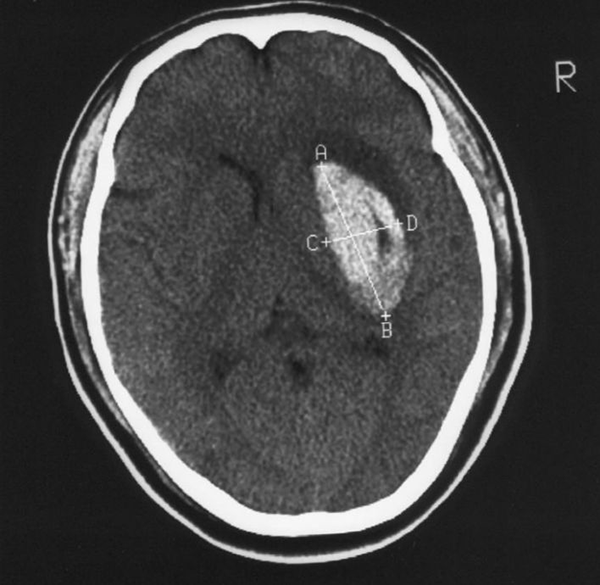

優(yōu)勢(shì)學(xué)科|高血壓腦出血外科手術(shù)治療方案介紹

多數(shù)人對(duì)高血壓疾病并不陌生,甚至部分人群患有本病,可能引起心腦血管疾病。腦出血是在非外傷腦實(shí)質(zhì)內(nèi)血管破裂因素的影響下,腦部出現(xiàn)的出血現(xiàn)象,在腦卒中疾病中,發(fā)生機(jī)率高達(dá)20%~30%。腦出血死亡機(jī)率較高,即便幸存,也會(huì)伴有不同程度的運(yùn)動(dòng)、認(rèn)知、言語障礙后遺癥,降低患者生活品質(zhì)。而高血壓腦出血發(fā)病急促,進(jìn)展速度快,死亡和殘疾率高,對(duì)人們健康無疑是巨大威脅。

高血壓腦出血的手術(shù)方案

骨瓣開顱血腫清除手術(shù)是臨床以往常用的一種治療手段,手術(shù)視野較大,可以充分發(fā)現(xiàn)原發(fā)病灶,精準(zhǔn)止血,幫助患者完全清除血腫組織,糾正腦血流灌注狀態(tài),結(jié)合病情程度,合理去骨瓣糾正顱內(nèi)高壓狀態(tài),改善腦疝患者腦干壓迫度,提高患者生存質(zhì)量,但是手術(shù)過程中,需要開顱,對(duì)患者的創(chuàng)傷性較大,術(shù)中出血量大,手術(shù)時(shí)間長(zhǎng),可能需要二次開展顱骨修補(bǔ)術(shù),在一定程度加重病人經(jīng)濟(jì)負(fù)擔(dān),而且老年、體質(zhì)較弱的病人,對(duì)這種手術(shù)的耐受度極低,無法順利實(shí)施。

小骨窗開顱血腫清除手術(shù)的應(yīng)用,可以在一定程度上彌補(bǔ)骨瓣開顱血腫清除術(shù)大創(chuàng)傷性的不足,影像技術(shù)定位血腫部位,就近作3cm小骨窗進(jìn)行手術(shù)操作,微創(chuàng)特征明顯,操作相對(duì)簡(jiǎn)單,能夠直視觀察血腫組織并良好清除,確保腦部重要部位功能,避免醫(yī)源損傷,但是術(shù)后并發(fā)癥也較多,同時(shí)無法應(yīng)用在腦疝和深部出血患者治療中,往往對(duì)出血量少、淺表性出血病人更有治療優(yōu)勢(shì)。

立體定向錐顱血腫引流手術(shù)也需借助影像技術(shù)手術(shù)定位、穿刺、置管,保證血腫中心合理放置引流管,良好引流。此種手段操作相對(duì)簡(jiǎn)單,手術(shù)用時(shí)短,不會(huì)對(duì)患者產(chǎn)生較大影響,同時(shí)無全身麻醉處理,可適當(dāng)減少經(jīng)濟(jì)花費(fèi),但是盲目性是這種手術(shù)方案的主要缺點(diǎn),無法直視操作,臨床往往將其應(yīng)用在病情輕、血腫量小的病人治療方案中。

神經(jīng)內(nèi)鏡輔助血腫清除手術(shù)仍需影像技術(shù)定位引導(dǎo),鉆顱孔置入神經(jīng)內(nèi)鏡于血腫腔內(nèi),直視作用突出,操作簡(jiǎn)單,能盡早清除腦部血腫,減少出血,術(shù)后早期恢復(fù)。而這種手術(shù)方案的缺陷在于手術(shù)空間較小、視野相對(duì)狹窄、血凝塊會(huì)干擾清晰度、難以完全止血、價(jià)格較高,所以臨床難以普及應(yīng)用,可作為將來重要發(fā)展點(diǎn)。

神經(jīng)導(dǎo)航輔助微創(chuàng)手術(shù)是一種新型手術(shù)方案,開創(chuàng)了神經(jīng)外科廣泛發(fā)展前景。計(jì)算機(jī)動(dòng)態(tài)結(jié)合病人頭部影像資料和病灶,實(shí)時(shí)性和精準(zhǔn)性特征明顯,醫(yī)師能夠明確手術(shù)部位和病灶之間的關(guān)系,確保手術(shù)視野,動(dòng)態(tài)導(dǎo)航式評(píng)估調(diào)整手術(shù)方案,避免過度損傷患者組織,減少術(shù)后并發(fā)癥發(fā)生風(fēng)險(xiǎn)。此種手術(shù)優(yōu)勢(shì)雖多,如精準(zhǔn)、手術(shù)用時(shí)短、安全有效,不會(huì)損傷周圍腦部組織,但是高要求神經(jīng)導(dǎo)航技術(shù),經(jīng)濟(jì)費(fèi)用高,無法普及在普通或基層醫(yī)院,是今后神經(jīng)外科高血壓腦出血手術(shù)的重要發(fā)展方向。